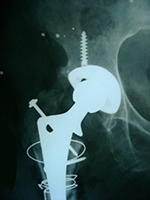

Post-Traumatic - CASE 1